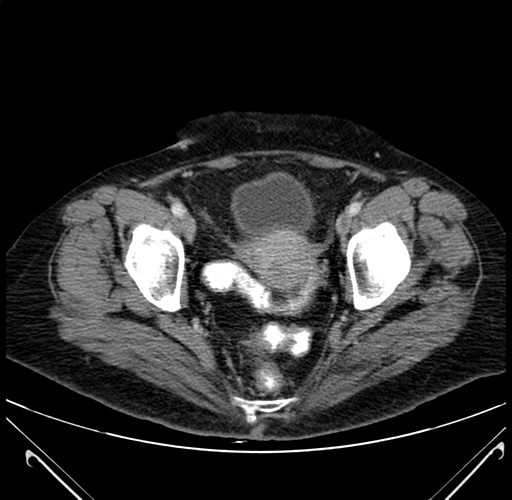

Axial Venous